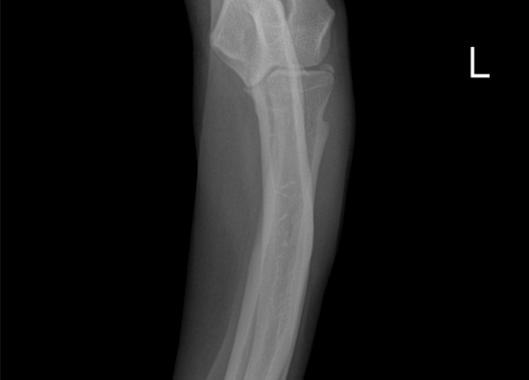

요척골 복합만곡기형 수술 전

요척골 복합만곡기형 수술 후

정형외과 케이스

본원은 실력 있는 전문 의료진과 최첨단 시설로 정형외과에서 좋은 예후들을 보여드리고 있습니다. 강아지에게서 쉽게 발생하는 슬개골 탈구, 십자인대 단열 뿐 아니라 다양한 고난도 케이스를 다루고 있으며, 특히 골절 수술은 회복률이 높고 타원 수술 후, 유합부전으로 본원에 내원하여 재수술에 성공한 사례가 많습니다.